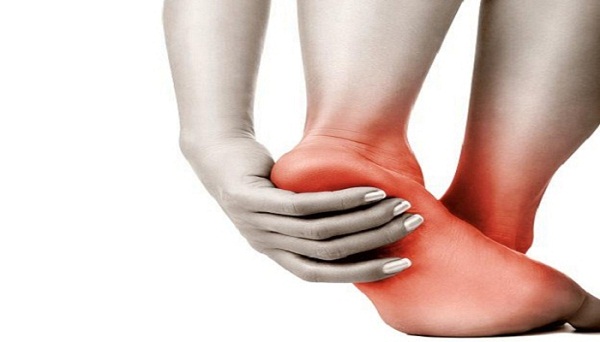

नई दिल्ली : वैसे एड़ियों का दर्द किसी को भी हो सकता है, लेकिन महिलाओं को एड़ियों का दर्द बेहद परेशान करता है। यह दर्द सुबह-सुबह बिस्तर से ज़मीन पर पैर रखते समय और भी ज्यादा होता है। एड़ियों में दर्द का मुख्य कारण प्लानटर फैसिटिस होता है, इस परिस्थिति को हील स्पर सिंड्रोम भी कहते है। इसके अलावा एड़ियों में दर्द के कई और कारण भी हो सकते हैं जैसे- स्ट्रेस,फ्रैक्चर, टेंडोनाइटिस और अर्थराइटिस के कारण भी हो सकता है। एड़ियों का दर्द आपकी सारी दिनचर्या को प्रभावित कर सकता है।

आमतौर पर एड़ियों का दर्द कुछ समय में ही दूर हो जाता है, लेकिन कई मामलों में ऐसा देखा गया है कि टखनों, मांसपेशियों और जोड़ों में सूजन लंबे समय तक बना रहता है. जिसकी वजह से कुछ भी काम करने में दिक्कत होती है. ऐसे में आपके लिए जरूरी है कि आप कुछ घरेलू टिप्स आजमाएं, जिससे ये समस्या खत्म हो. तो चलिए जान लीजिए इस नुस्खे को.